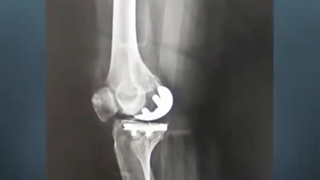

مراقبت های بعداز جراحی تعویض مفصل زانو